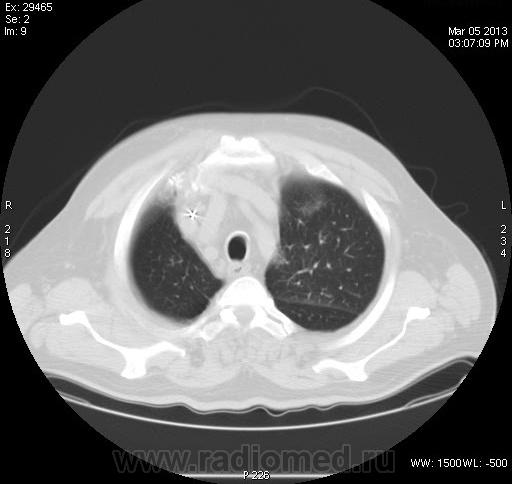

Непонятка КТ ОГК.

Задыхается, кашляет, Т-37, КТ "Cito!", рентгенограмм нет. В поликлинике закл.:" Двухстороння пневмония, МТС?"

Анализ изображений КТ исследования ОГК обязательно должен проводиться в двух окнах (легочном и медиастинальном). А в диф. плане, так еще  и с контрастированием. Есть ли возможность хотя бы увидеть изображения во втором режиме: для оценки участков консолидации, наличия кавтации, оценки л/узлов и средостения в целом...?

зон консолидации и лимфоузлы средостения. Похоже на саркоидоз. Тогда у  пациента не должно быть особых жалоб.

Не повезло больному. 11.03.2013г. умер в реанимации, сегодня только узнал. Причина смерти- множественные инфарт- пневмонии?!. Завтра выложу все, что найду. Я в шокеsurprise! Писал диссеминацию по типу септической + БАР.

Что говорить о контрастном КТ исследовании, если даже КТ-изображения данного пациента не выставлены во втором (медиастинальном) окне; была бы возможность оценки характера участков конолидации легочной ткани, состояния лимфатических узлов и средостения в целом.  Почему то никто не отметил наличие катеторов в верхней полой вене и правом желудочке сердца, что косвенно должно было навести на тромбоэмболический процесс. Конечно, в данном случае, КТ исследование с болюсным контрастированием помогло бы в правильной диагностике.